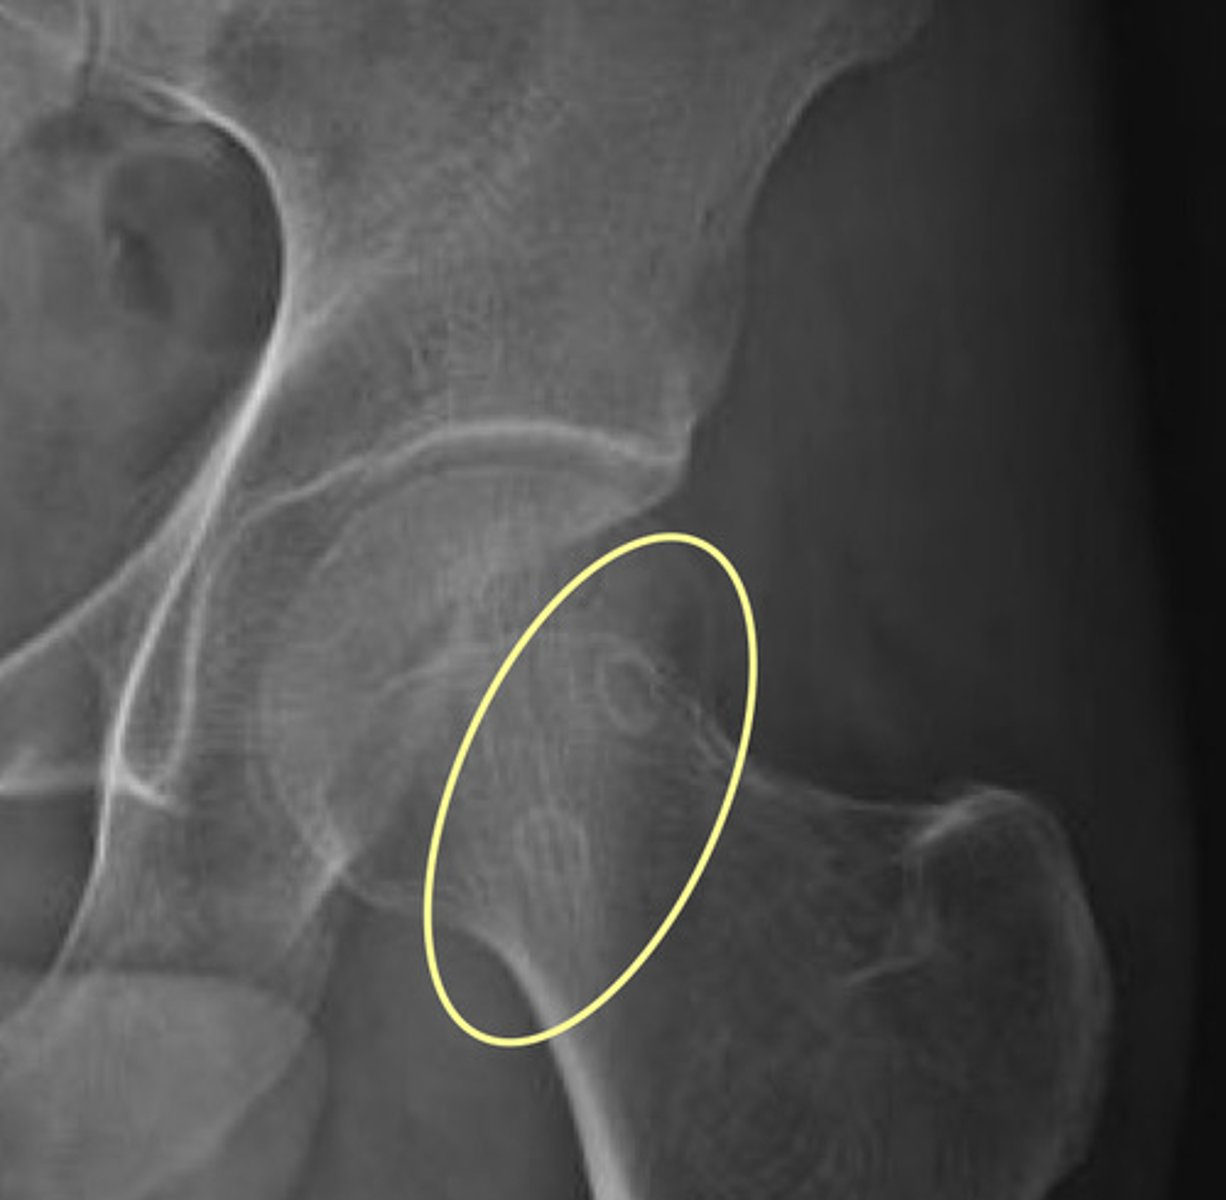

Femoral Herniation Pits

Notice denser, cortical bone around the pit

Clinical Significance of Femoral Herniation Pits

Incidental findings with no clinical significance = "leave it alone lesion"

Pits may enlarge over time